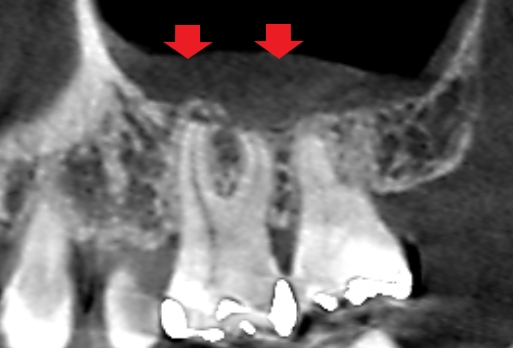

初診時のCT画像です。

赤い矢印の先に均一で薄い白い像がみられます。上顎第一大臼歯の歯髄の壊疽が原因で上顎洞の粘膜が炎症を起こし、上顎洞内で腫れあがっている状態と考えられます。